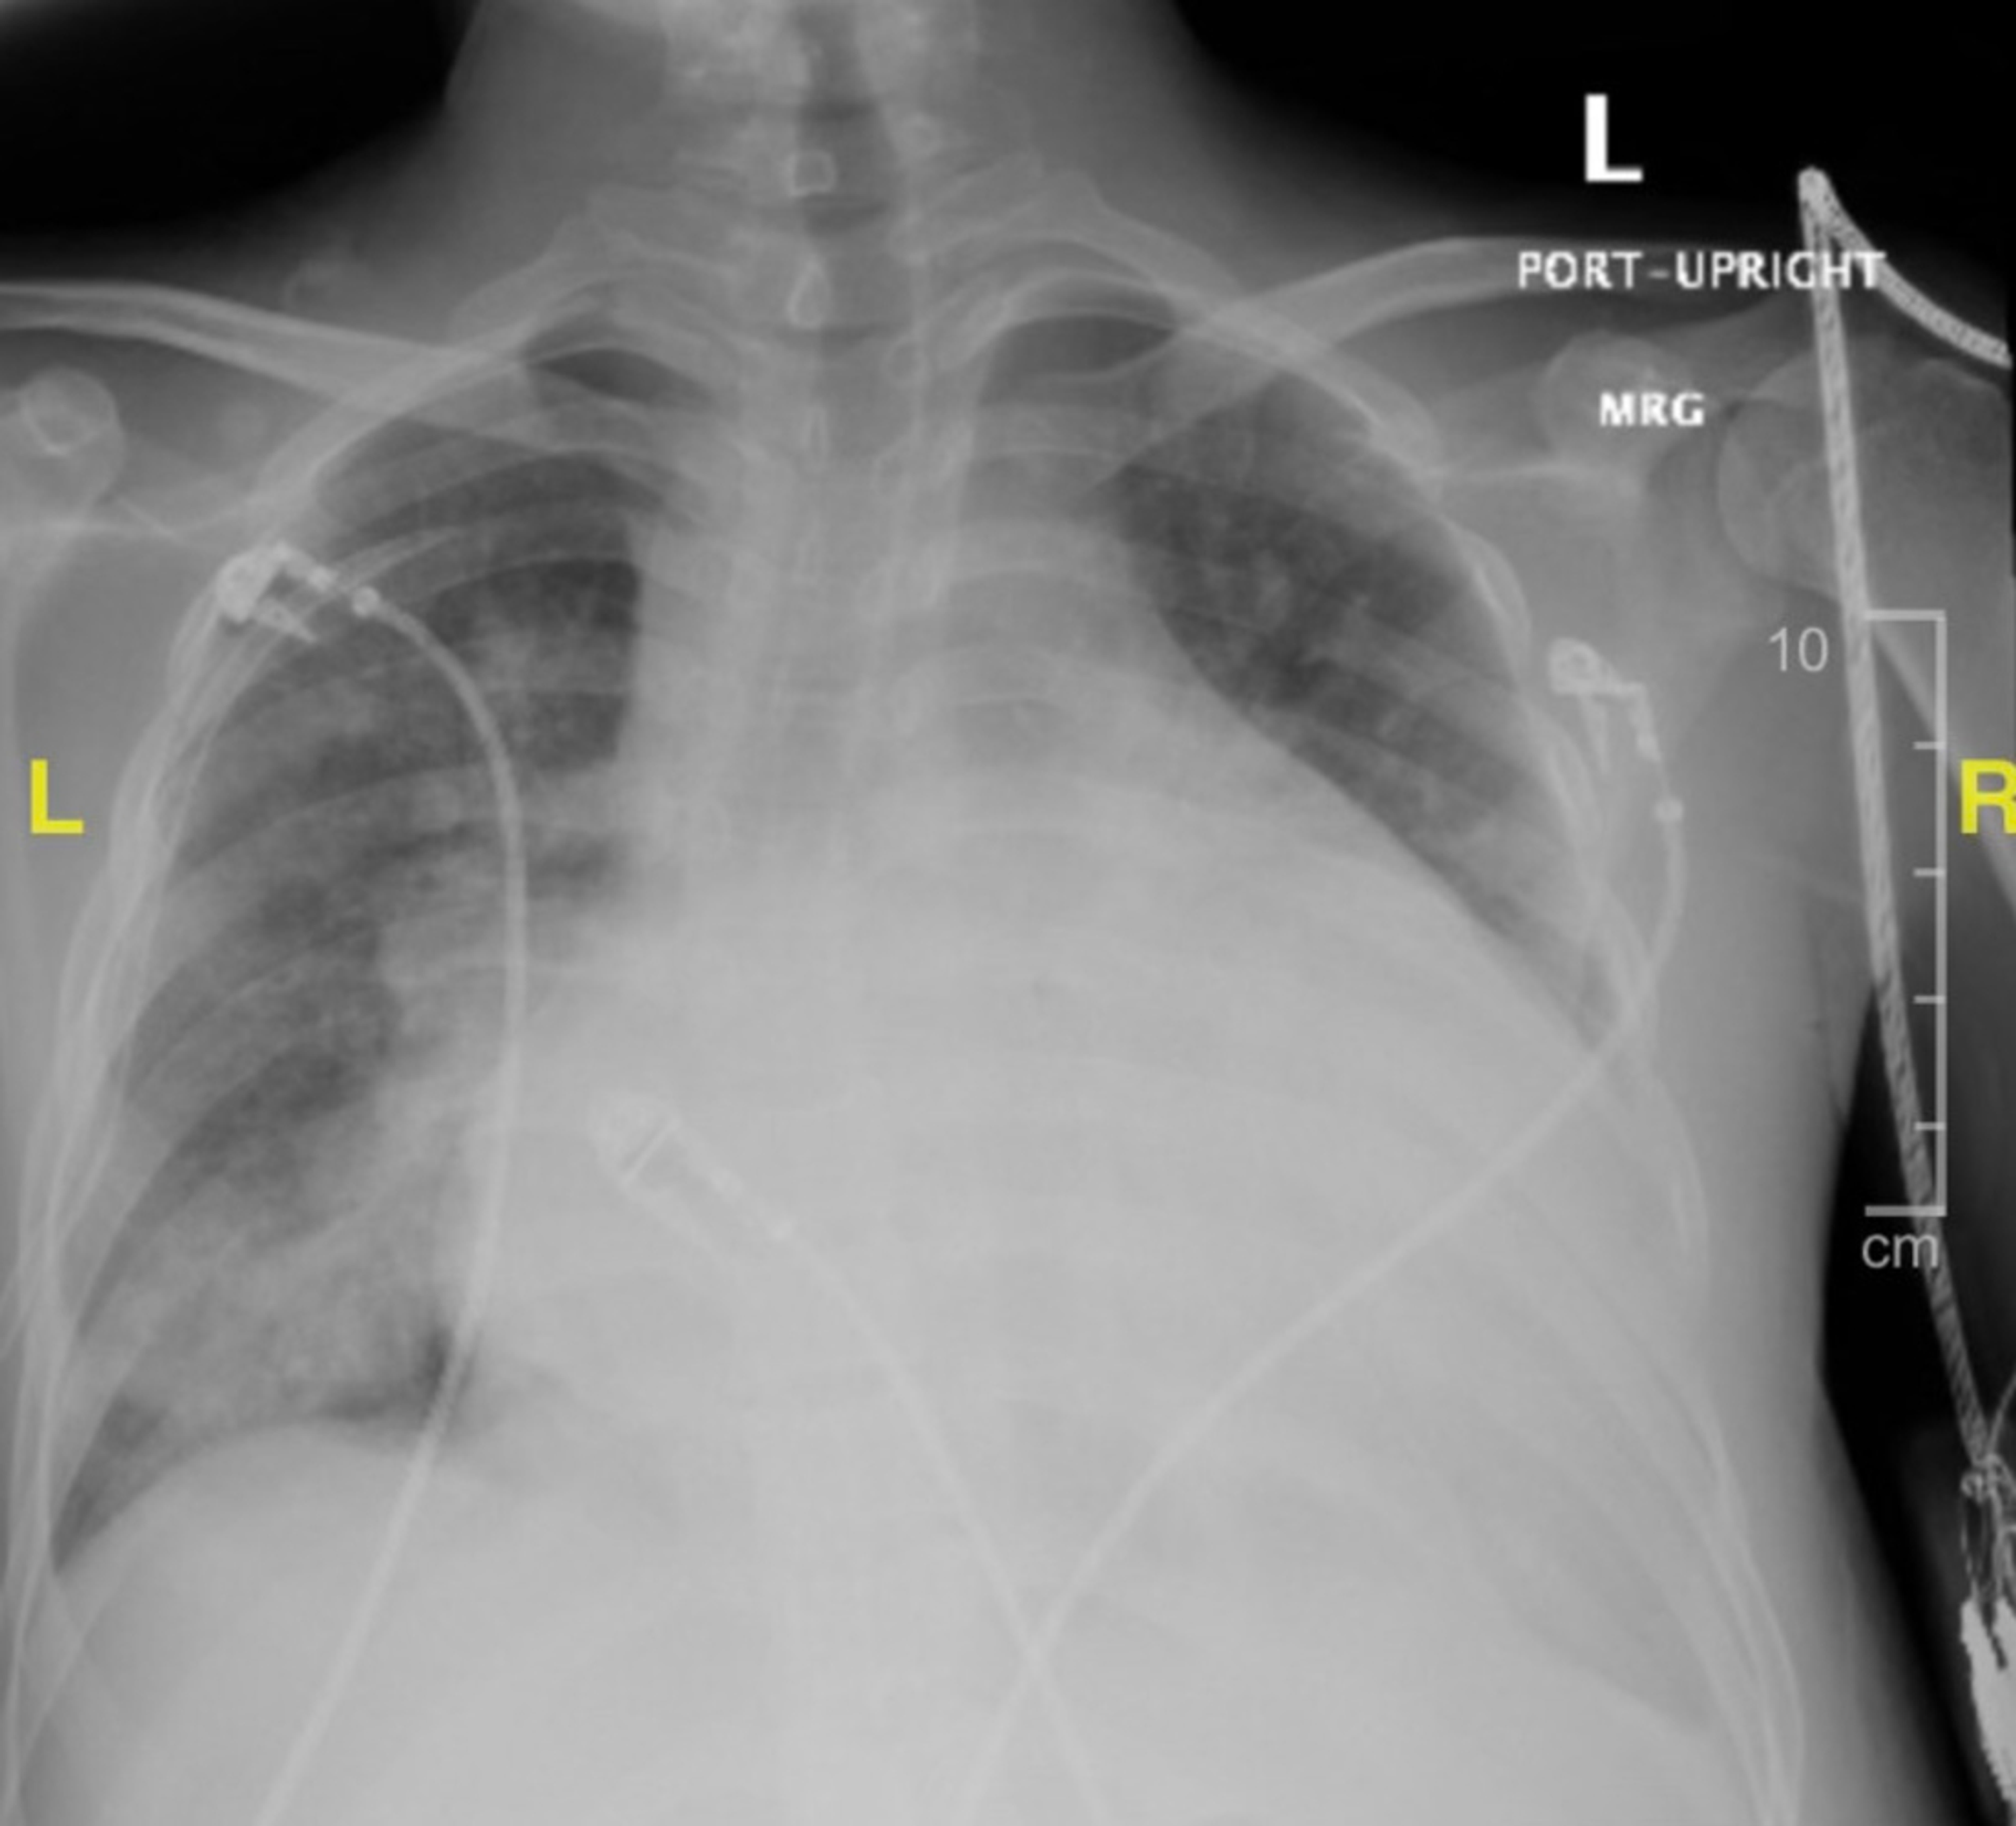

Chest X-Ray For Klebsiella Pneumoniae . classical klebsiella pneumoniae typically causes pneumonia (klebsiella pneumonia), lung abscess,. isolation of klebsiella pneumoniae is not sufficient evidence to establish it as the etiology in respiratory infections. klebsiella pneumoniae is a gram negative organism that usually affects people with alcoholism or chronic debilitating. chest radiography is generally the first imaging modality used for the evaluation of pneumonia. these radiographs demonstrate the predilection for involvement of the posterior segment of the right upper lobe in k.